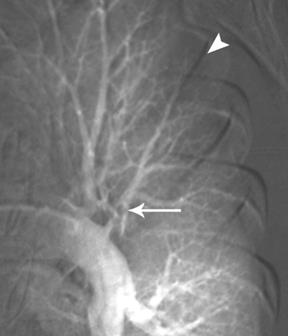

Острая эмболия. На ангиограмме левого лёгкого виден дефект в сосуде заднего сегмента (стрелка). Уменьшение перфузии в 3-ёх сегментарных артериях верхней левой доли (короткая стрелка)

Рис. 6

При тромбоэмболии легочных артерий ангиопульмонографию выполняют экстренно на фоне интенсивных реанимационных мероприятий. При общей ангиопульмонографии рентгеноконтрастный препарат вводят (чаще через катетер) в верхнюю полую вену, правые предсердие и желудочек либо через локтевую, подключичную и бедренную вены с той или другой стороны. При селективной ангиопульмонографии под контролем рентгенотелевидения катетер проводят по нижней (через бедренную вену) или верхней (через вены верхней половины тела) полым венам, правому предсердию и желудочку в легочный ствол, куда и вводят рентгеноконтрастный препарат. Катетер может также быть введен в правую или левую легочную артерию и в сосуды меньшего порядка. При ангиопульмонографии при необходимости выполняют лечебные процедуры, например через катетер удаляют тромб легочной артерии или размягчают его ферментами.